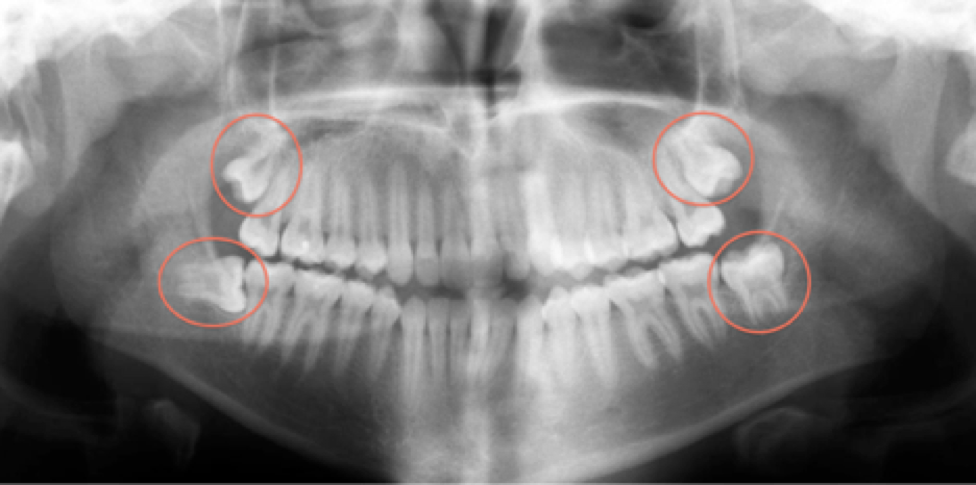

Ever had that nagging thought about what it’ll be like to speak after wisdom teeth extraction? You’re not alone. Many people wonder if they’ll be able to chat right away or if they’ll be stuck in a silence zone for days. If you’re scheduled for this procedure or just had it, you’re likely pondering the same thing. Well, let’s dive into the nitty-gritty and answer that burning question: can you talk after wisdom teeth removal?

In this blog, we’ll explore the ins and outs of post-wisdom teeth removal, focusing on swelling, numbness, and how these factors can affect your speaking abilities. We’ll also touch on why choosing Mahogany Oral Surgery in Calgary, AB, is your best bet for a smooth recovery.